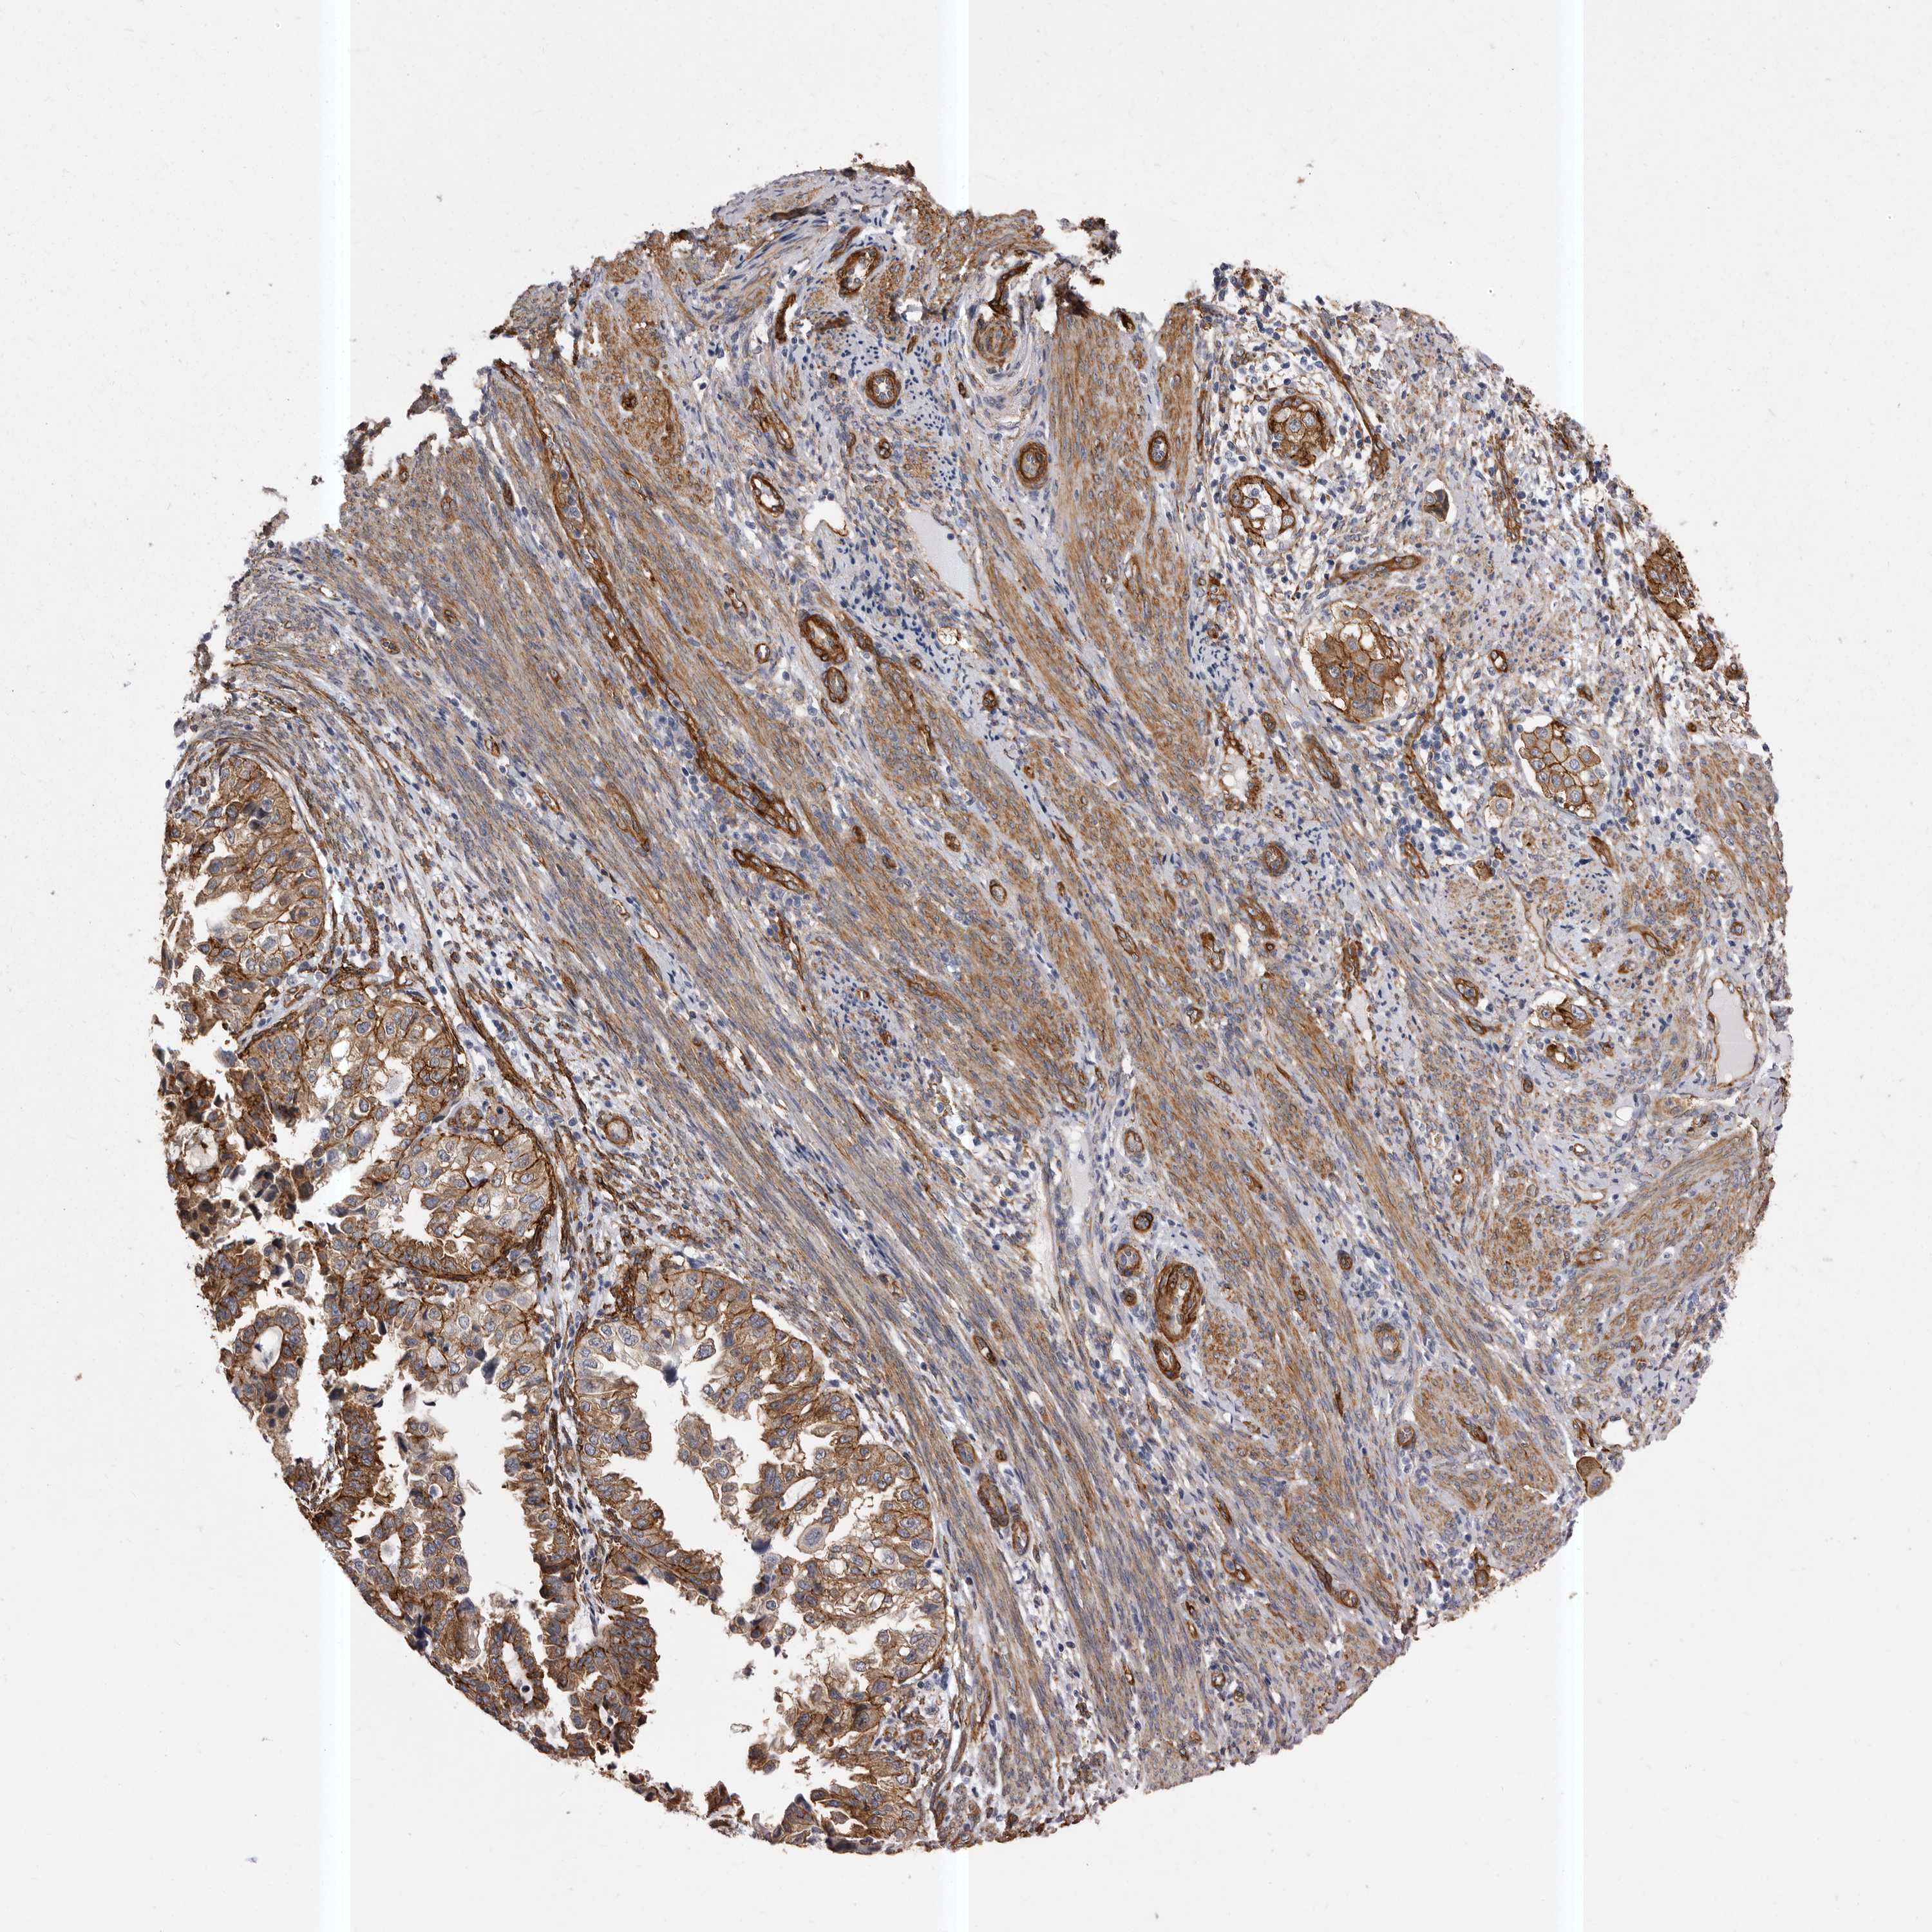

ENDOMETRIAL CANCER - Protein expressioni

A mouse-over function shows sample information and annotation data. Click on an image to view it in a full screen mode. Samples can be filtered based on level of antibody staining by selecting one or several of the following categories: high, medium, low and not detected. The assay and annotation is described here.

Note that samples used for immunohistochemistry by the Human Protein Atlas do not correspond to samples in the TCGA dataset.

Antibody stainingi

Antibody staining in the annotated cell types in the current human tissue is reported as not detected, low, medium, or high, based on conventional immunohistochemistry profiling in selected tissues. This score is based on the combination of the staining intensity and fraction of stained cells.

Each image is clickable and will lead to virtual microscopy that enables deeper exploration of all samples and also displays staining intensity scores, fraction scores and subcellular localization as well as patient and tissue information for each sample.

Antibody HPA028448

Antibody HPA028696

Staining

High

Medium

Low

Not detected

Intensity

Strong

Moderate

Weak

Negative

Quantity

>75%

75%-25%

<25%

None

Location

Nuclear

Cytoplasmic/membranous

Cytoplasmic/membranous,nuclear

Adenocarcinoma, NOS

Adenocarcinoma, metastatic, NOS